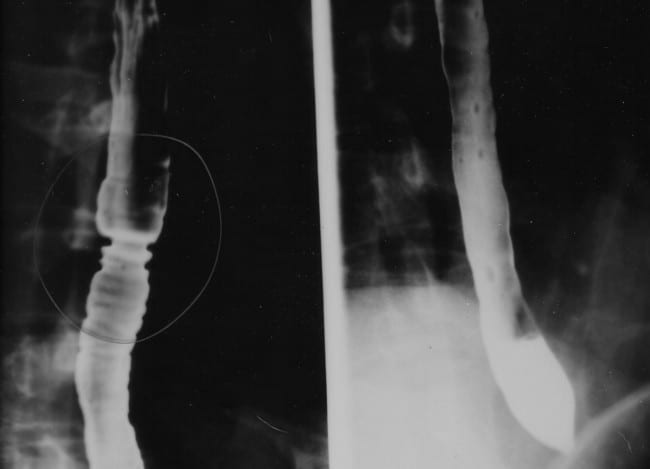

रेडियोग्राफिक तकनीक की मदद से इसोफैगस (फूड पाइप) और पेट की बीमारियों और विकारों के बारे में पता लगाने की तकनीक बेरियम स्वालो कहलाती है। अगर आपको खाना निगलने में परेशानी हो या फिर पेट में असमान दर्द हो और उल्टी में खून आ रहा हो तो बेरियम स्वालो टेस्ट से इसका कारण पता लगाया जा सकता है। इस टेस्ट में बेरियम के मिश्रण को पिलाया जाता है और फिर ये मिश्रण शरीर के अंदर जाकर डाइजेस्टिव ट्रैक्ट के विकारों को उभार देता है जिससे एक्स–रे में वे साफ देखे जा सकते हैं।

बेरियम स्वालो टेस्ट को बेरियम एसोफैगोग्राम (Esophagogram) या एसोफैगराम (Esophagram) भी कहा जाता है।

बेरियम मिश्रण पिलाने से पहले एक्स–रे किया जाएगा। इसके बाद धीरे–धीरे आपको बेरियम सोल्यूशन पीने के लिए कहा जाएगा। अंत तक आपको लगभग 240 मिलीलीटर (एक कप) मिश्रण पिला दिया जाएगा।

रेडियोलाजिस्ट शरीर के अंदर बेरियम को गैस्ट्रोइंटेस्टाइनल ट्रैक्ट से गुजरते हुए देखेंगें। इस वक्त आपको हल्का झुकने के लिए कहा जाएगा ताकि मिश्रण पूरी तरह से फैल सके।इस दौरान हल्के हाथ से डॉक्टर पेट पर दबाव भी बनाएंगें जिससे खासी के दौरान भी शरीर के अंदर आने वाले बदलावों को देखा जा सके। अगर आपके शरीर के छोटे हिस्से को ही देखना है तो लगभग 30 मिनट का समय लगेगा। हर 30 मिनट में एक्स – रे निकाला जाएगा। कई बार गहरी जांच के लिए डॉक्टरआपको 24 घंटे बाद भी बुला सकते हैं ताकिऔर तस्वीरें ली जा सकें।